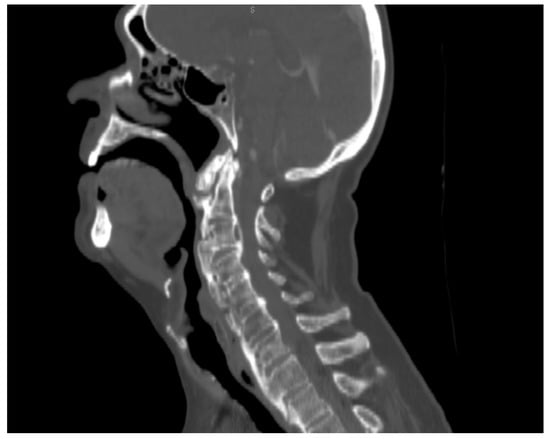

We performed a lateral–cervical spinal X-ray, a CT scan (Figure 2), and MRI (Figure 3) of the head, neck, and chest, which demonstrated anterior osteophytosis resulting in the compression of the esophagus between levels C2 and C5 and widespread axial spondylarthrosis. We also performed an esophago-gastric endoscopy, which showed a normal and undamaged esophagus, with whitish-pink cardiac mucosa and no motility disorders (Figure 4); in addition, the lumen appeared to present an ab extrinsic compression at its proximal tract. Given the absence of upper digestive endoscopy abnormalities, we initiated a logopedic and postural rehabilitative treatment.

Figure 1. Sagittal CT: hyperostotic anterior longitudinal spinal ligament with large osteophytes compressing the aerodigestive tract. The lesion extended from C2–C5.